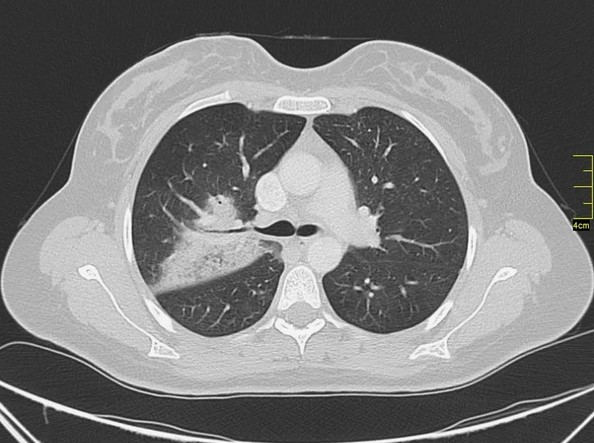

Легочные кальцинаты

Наличие образований в органах дыхания может проявиться в виде учащения дыхания, одышки и посинения кожных покровов. Кальцинаты в легких нередко возникают после перенесенной пневмонии или туберкулеза. Также сопутствует их формированию легочный гельминтоз.

УЗИ редко применяют для выявления кальцификатов. Образования на изображении выглядят как уплотнения или сгустки с тенью. Ультразвуковое исследование не такое эффективное, как 2 предыдущих, однако его тоже применяют для выявления кальциноза.

Компьютерная томография позволяет диагностировать точное размещение и размеры солевых отложений.

- МРТ. Магнитно-резонансная томография является наиболее информативным и простым способом диагностики. Во время проведения процедуры на мониторе отображаются кальцинаты в трехмерном виде. К недостаткам этого метода обследования относят высокую стоимость. Альтернатива МРТ – рентген снимок. При наличии кальцификатов в печени врач видит образования, которые имеют высокий уровень плотности.

- УЗИ. Применяется в редких случаях. Во время обследования при помощи УЗИ врач не может точно определить форму и вид кальцинатов. На мониторе видны только уплотнения или сгустки, которые дают тень. Ультразвук применяют в комплексе с другими методами.